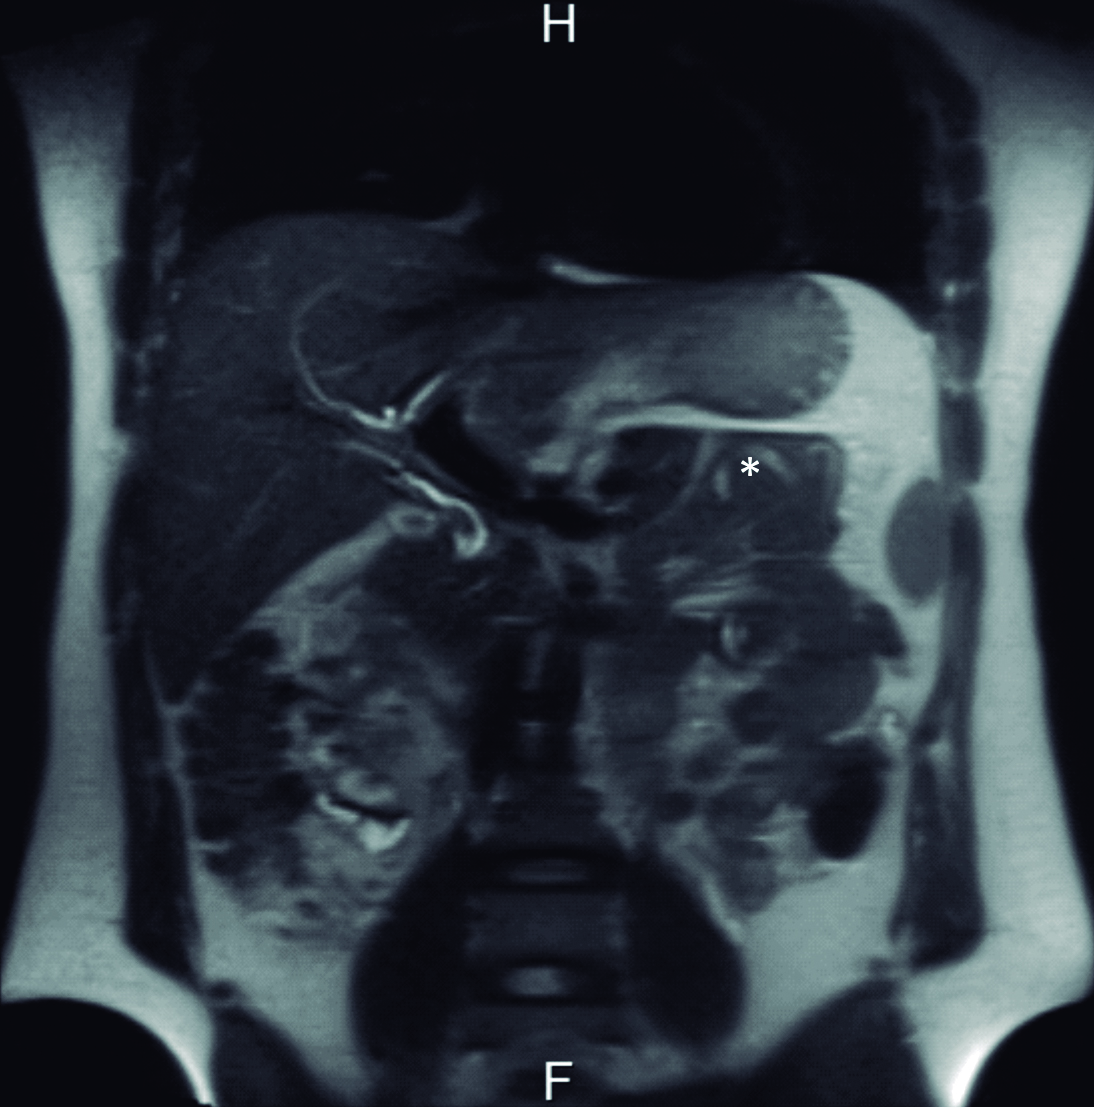

Se interroga a la paciente y refiere haber sido estudiada previamente con una colangiografía por resonancia magnética tres meses previo a la consulta en otro centro hospitalario. En ese momento la vía biliar principal no estaba ocupada. Retrospectivamente se identificaron los parásitos en el tubo digestivo proximal (Fig. 4 y 5).

Figura 4. Resonancia Magnética

a y b) Imágenes en plano coronal potenciadas en T2 sin saturación grasa. A nivel de asas yeyunales proximales se identifican los parásitos como imágenes lineales ligeramente hiperintensas con un área central hipointensa (*).

La resonancia magnética es una excelente modalidad no invasiva para diagnosticar la presencia de parásitos en la vía biliar. En imágenes ponderadas en T1, los gusanos se ven como estructuras tubulares lineales ligeramente hiperintensas con un área central hipointensa y en la colangiografía por resonancia se visualizan como defectos lineales de relleno hipointensos en el tracto biliar. (4, 9, 10)